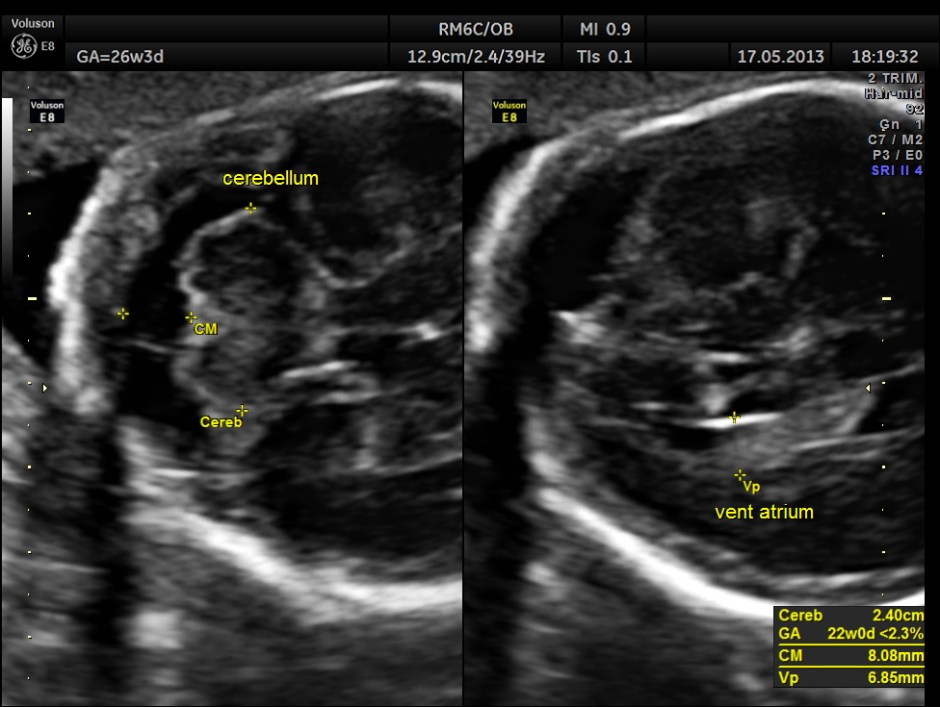

The images are given below.

Cerebellum appears relatively smaller and corresponds to a GA of 22 to 23 weeks. Usually the cerebellum corresponds very closely to the GA and would be very useful to follow in cases of IUGR.

Cerebellum was < 2.3 %tile , suggestive of possible cerebellar hypoplasia. Unfortunately this patient was lost for follow up .